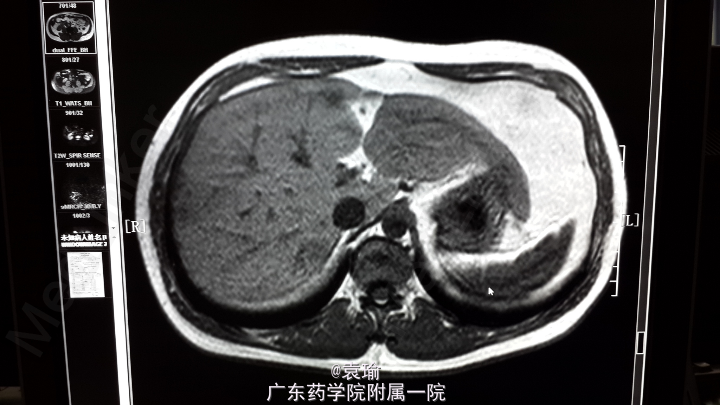

辅助检查:多次血常规检查见嗜酸性粒细胞计数及比例增高(见附图),肝功能检查异常(见附图),超敏C反应蛋白6.200mg/L,降钙素原0.076ng/ml,余大、小便常规正常,多次大便找虫卵阴性,肾功能、凝血功能、血脂均正常,肿瘤指标(AFP、CEA、Ca-199、CA-125、CA-724、CA-153)均正常,胃镜检查示非萎缩性胃炎轻度,多点活检未见明显嗜酸性粒细胞浸润。腹部MR+MRCP:肝内多发异常信号影,考虑感染性病变,注意寄生虫感染可能,MRCP未见异常。

该病例急性起病,影像学检查见肝内多发占位性病变,对占位病变的性质不确定,结合多次血常规检查嗜酸性粒细胞明显增多,且患者有进食“鱼生、螺肉”等流行病学史,故高度怀疑寄生虫感染可能,但因进一步确诊存在困难,遂予诊断性治疗,短期内血常规好转,支持诊断。 提出该病例,请各位有相关治疗经验的同道对诊治过程进行指正,了解有无其他可明确诊断方法,并对进一步治疗提出指导意见,多谢!